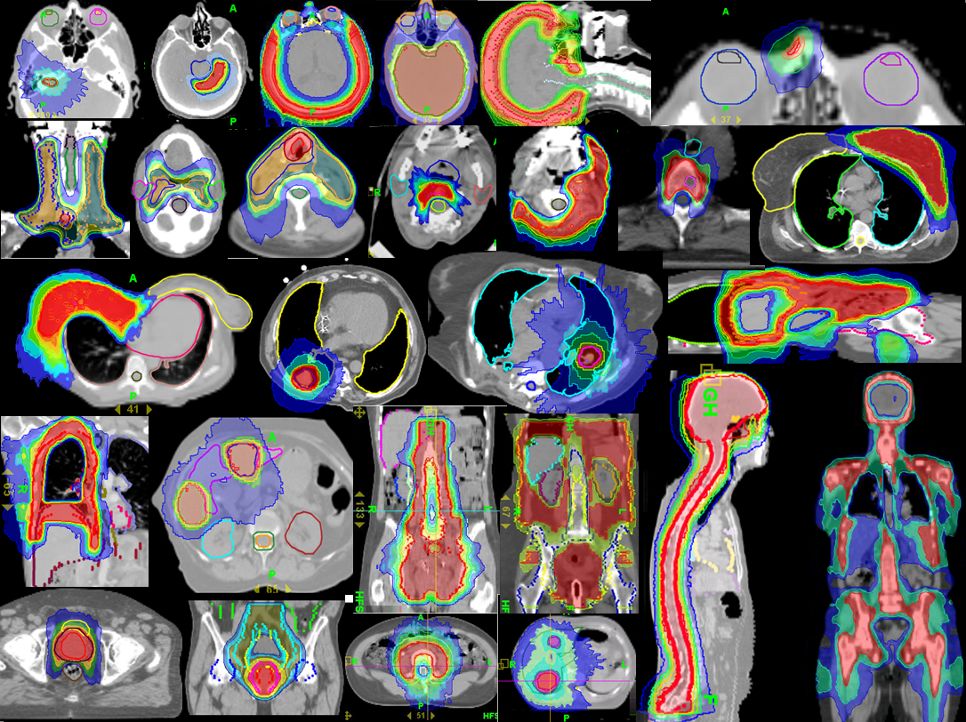

放射治疗是癌症治疗的常规方法,大约一半的患者在治疗过程中需要接受放射治疗,这种治疗使用高能辐射来缩小肿瘤并杀死癌细胞,然而传统意义的放疗不够精准,副作用较大,目前国内一些最新的放疗技术能够实现更精准的治疗。

托姆刀tomotherapy(螺旋断层放射治疗系统)是集IMRT(调强适形放疗)、IGRT(影像引导调强适形放疗)、DGRT(剂量引导调强适形放疗)于一体,并能准确地控制照射的强度、方向、针对癌细胞的形态、大小进行“精确射击”,是一种先进的肿瘤放疗设备,目前国内大型三甲医院已引进,日本开展的时间较早,有丰富的临床经验。

与其他放疗设备相比,托姆刀最大的优势就是治疗的适应症极广,病灶不规则,巨大,全身多发转移灶等普通放疗和质子无法处理的病灶都可以通过托姆刀治疗。详情点击:托姆刀突破了被医学界视为“天方夜谭”的放疗瓶颈!

质子治疗技术经过半个实际的临床应用和研究,已被公认为是放疗领域先进的技术,被誉为“顶配版”放疗技术,由于其独有的布拉格峰,可以极快的速度穿透人体,并只在癌细胞特定部位释放出最大能量,将癌细胞杀死,而不会伤害周围正常组织,副作用小。目前,欧美、日本等发达国家越来越多的将质子治疗应用于肿瘤的治疗。